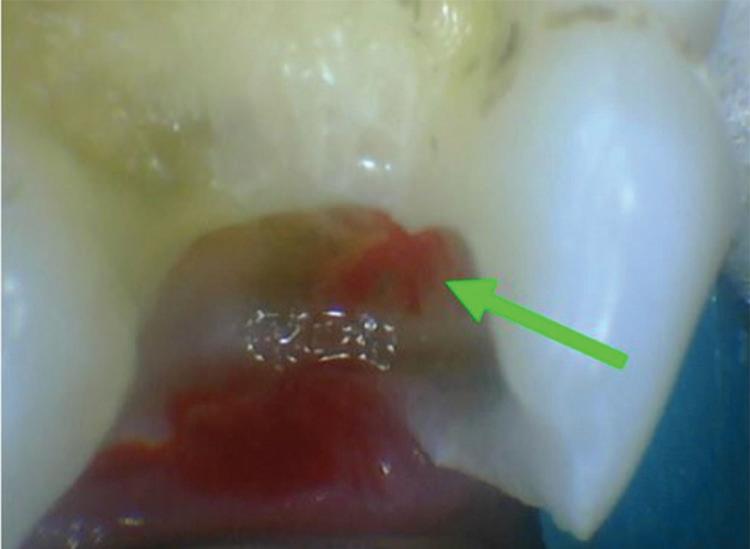

In the endodontic stage, conservative endodontic preparation and obturation with modern techniques are performed as they are for any tooth. All endodontic procedures are performed under an operating microscope to maximize visualization and illumination of the fracture line (Fig 1). The coronal portion of the newly placed gutta percha is removed 2 to 3 mm below the deepest extent of the crack in the affected canal to prepare for intraradicular barrier placement (Fig 2). Gutta percha is also removed 2 to 3 mm into the other noncracked canal orifices in the tooth to prepare for traditional orifice barriers. Microscopic transillumination with a fiber-optic light, in which an LED light probe is placed against buccal or lingual tissues overlying the roots, is utilized to illuminate the root and enhance visualization of the crack (Fig 3). A flowable resin-modified glassionomer or composite resin is then placed in this newly created void from the level of the gutta percha to the floor of the pulp chamber in all canal orifices (Fig 4). A composite resin core is then placed to permanently restore the endodontic access. If a temporary or permanent crown is not placed immediately after the endodontic procedures, the tooth is reduced

Fig 1. Microscopic visualization of the radicular extension of the crack (arrows) entering the canal.

Fig 3. Microscopic transillumination. A. Canal space viewed under microscopy without transillumination. B, C. Same canal viewed at different angles with the aid of a fiber-optic light. Transillumination reveals a root fracture.